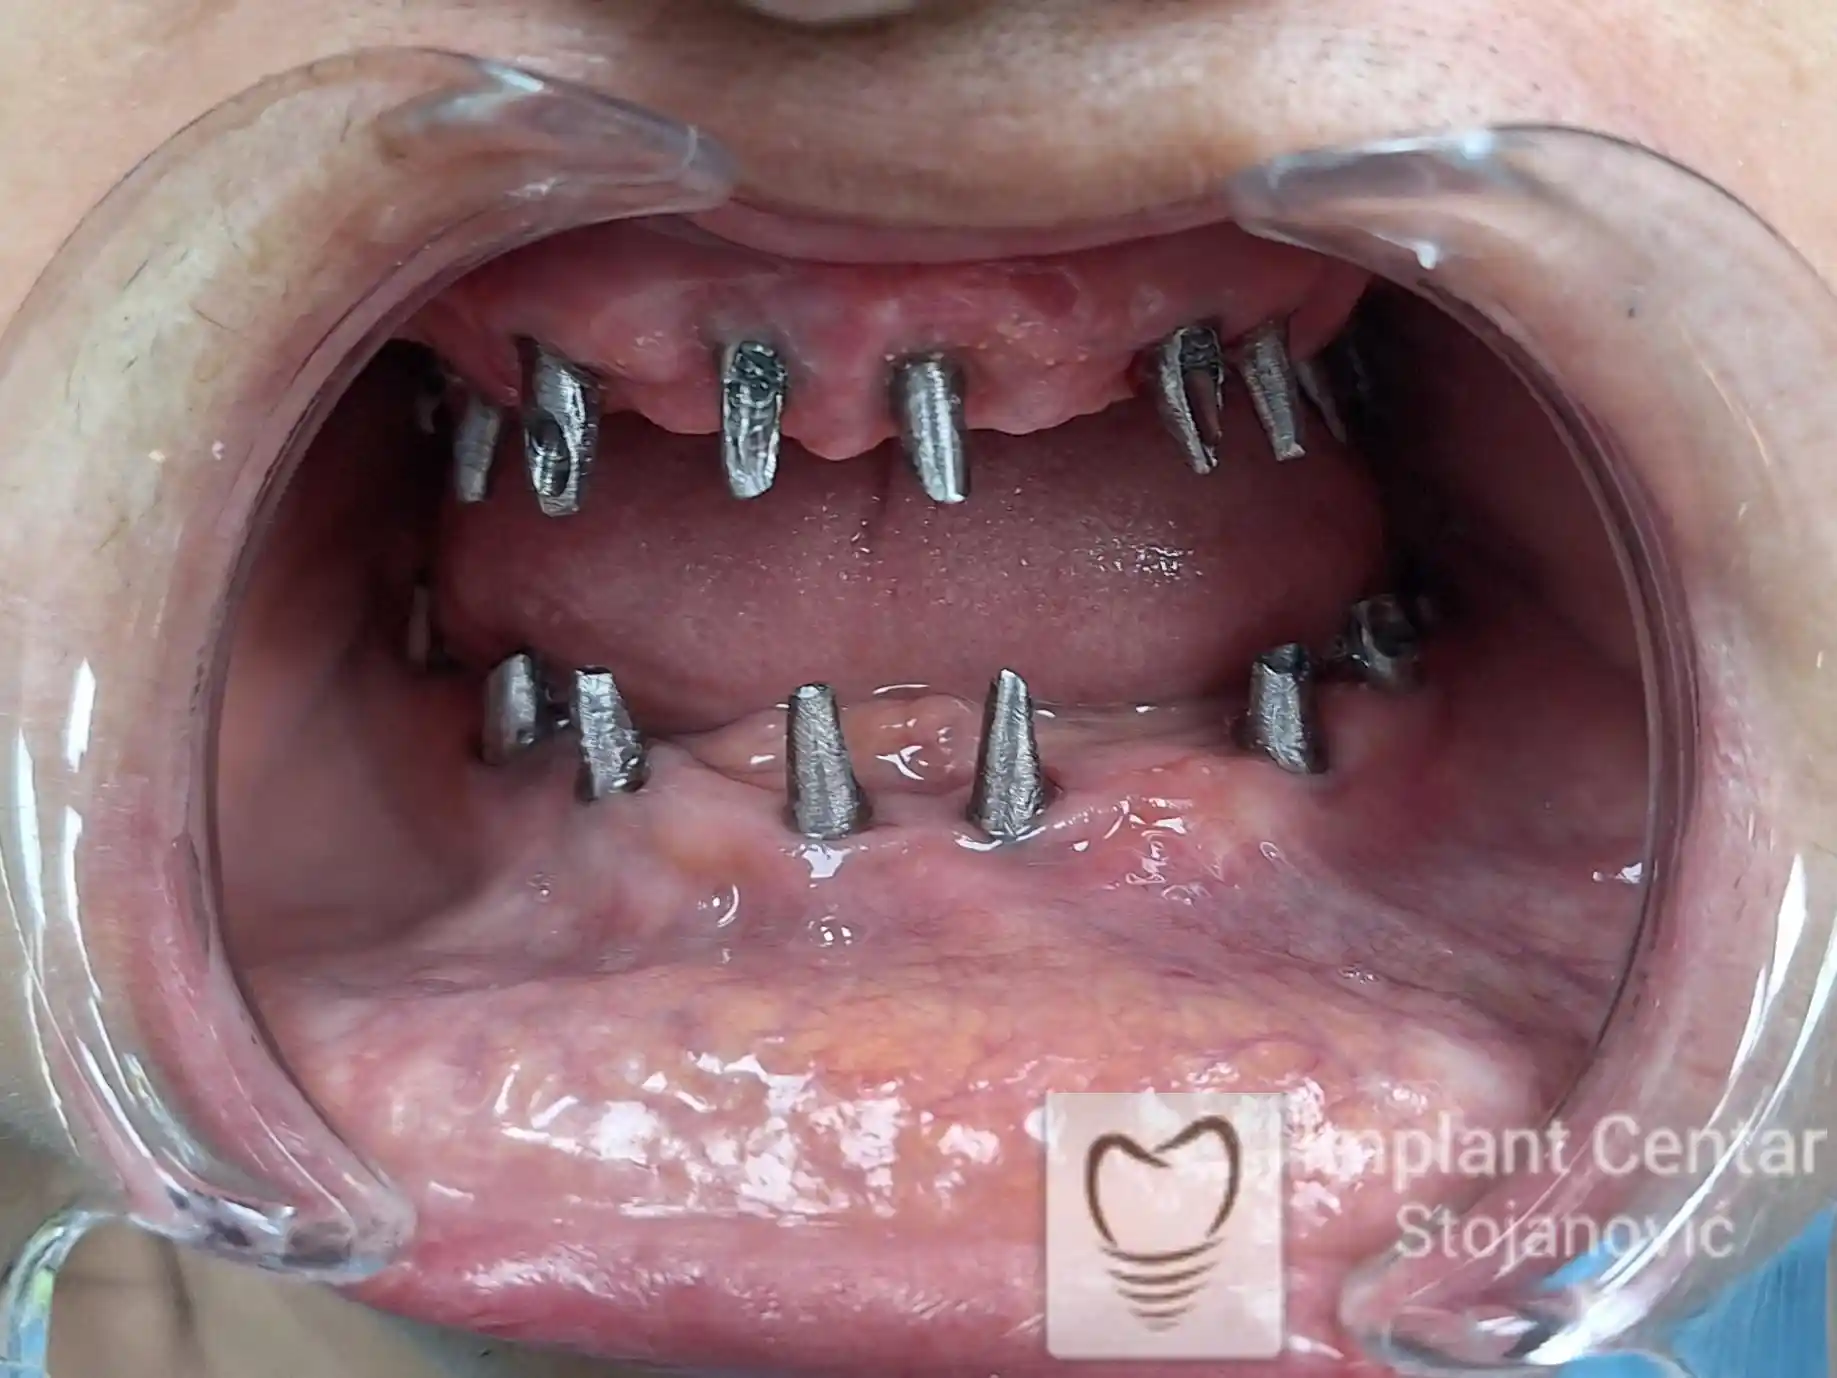

Pacijentkinja je došla sa dotrajalim mostovima i preostalim zubima loše biološke vrednosti, dok su bezubi prostori bili prisutni u gornjoj vilici sa desne strane i  u donjoj vilici sa leve strane. Nakon detaljnog kliničkog pregleda i analize snimaka, izvršeno je vađenje svih zuba i ugradnja optimalnog broja dentalnih implantata.

Već tri dana nakon operacije pacijentkinja je zbrinuta privremenim krunicama, kojima je bila oduševljena jer su odmah omogućile funkciju i estetiku. Nakon perioda oseointegracije izrađene su definitivne cirkonijum-keramičke krunice, čime je postignuta maksimalna estetika, funkcija i vraćeno samopouzdanje. Pacijentkinja je presrećna postignutim rezultatom.